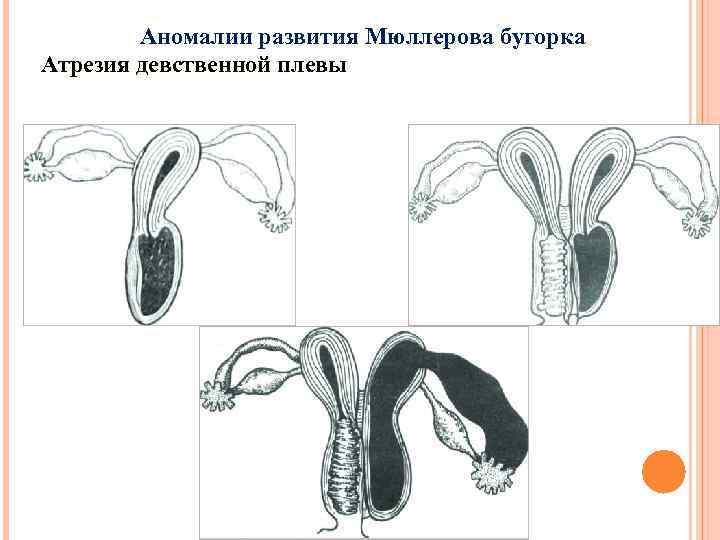

Аномалии развития Мюллерова бугорка Атрезия девственной плевы

Аномалии развития Мюллерова бугорка Атрезия девственной плевы